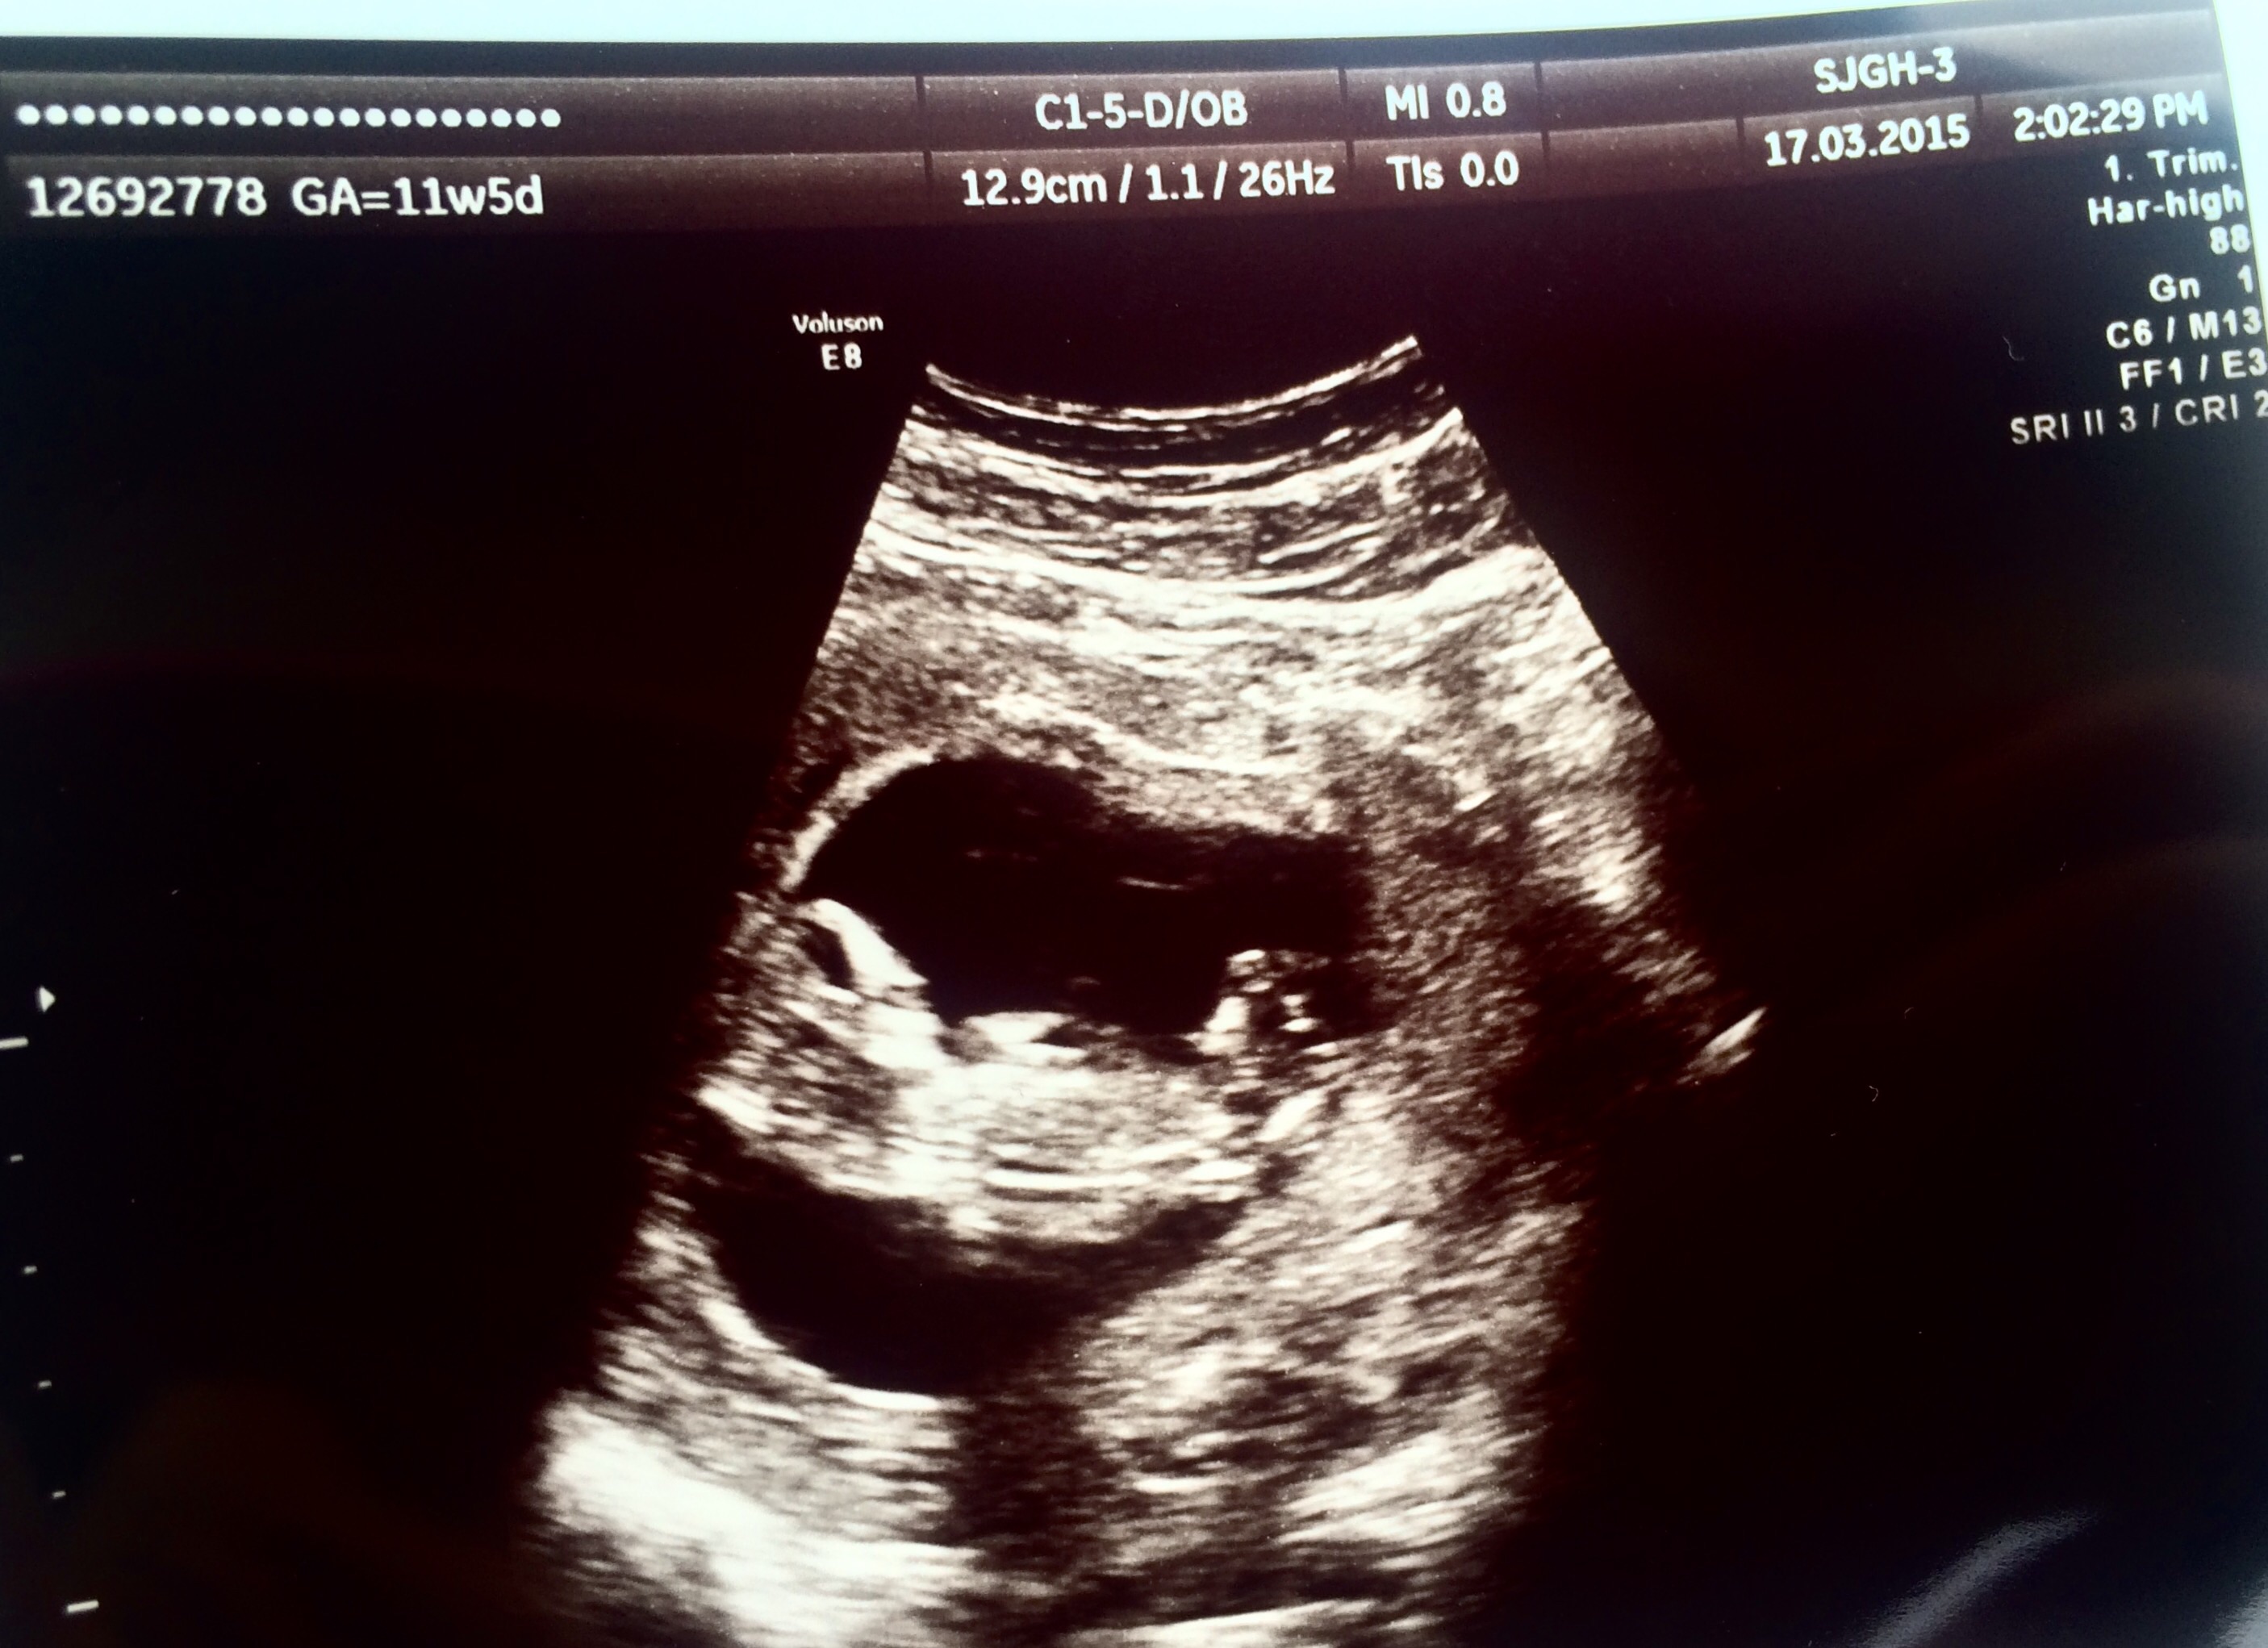

Taken some where in the middle of week 11, maybe week 12. One adoreable mini-me I do have a better one showing it's cute nose but that's lost somewhere in the pc atm.